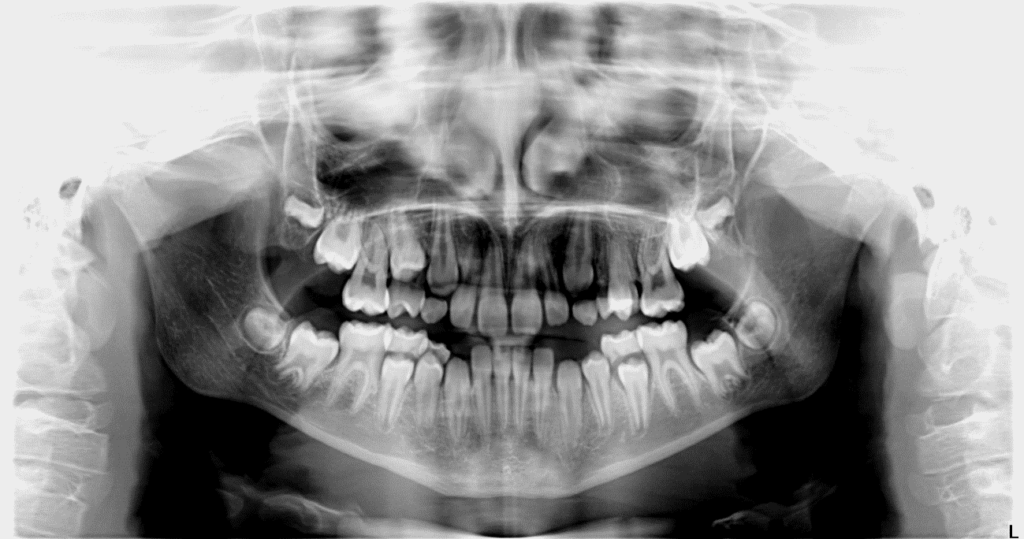

2. Ortopantomografia (OPT), detta anche radiografia panoramica, è un esame di I° livello, serve per verificare la presenza, lo stato e la posizione dei denti, fornisce valide informazioni di carattere generaleanche sulle ossa mascellari e mandibolari comprese le strutture anatomiche adiacenti.